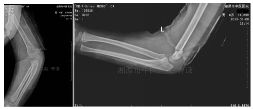

外院拍片情况如下:

GartlandⅢ型肱骨髁上骨折患者,患肢畸形、肿胀明显。肘前方可见皱褶,典型的难复型肱骨髁上骨折。